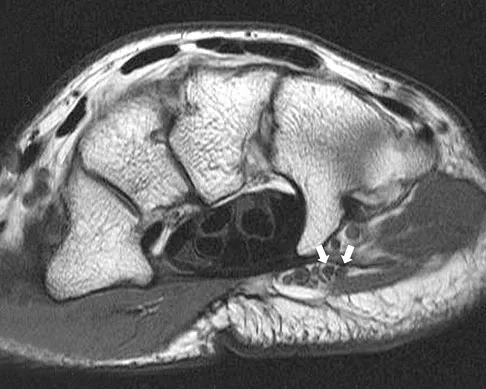

A 26-year-old man has recurrent right knee pain. Figures 9a and 9b show consecutive sagittal T2-weighted MRI scans, and Figure 9c shows a coronal T1-weighted MRI scan. What is the most likely diagnosis?